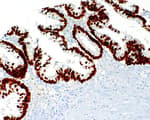

Mouse anti-Cytokeratin 18 Monoclonal Antibody [LDK18]

Bethyl Laboratories Catalog # A500-035A A500-035A-T A500-035ACF

ValidatedDocuments (6)Mouse anti-Cytokeratin 18 Monoclonal Antibody [LDK18]

Validation Performed

Pillar 2: Complementary Assays

Pillar 4: Biological Characteristics

Target: Cytokeratin 18

Reactivity: Human

Applications:

Platforms: COMET™

Host: Mouse

Conjugate:

Purity:

For ordering information, see our International Distributors

Product has been discontinued